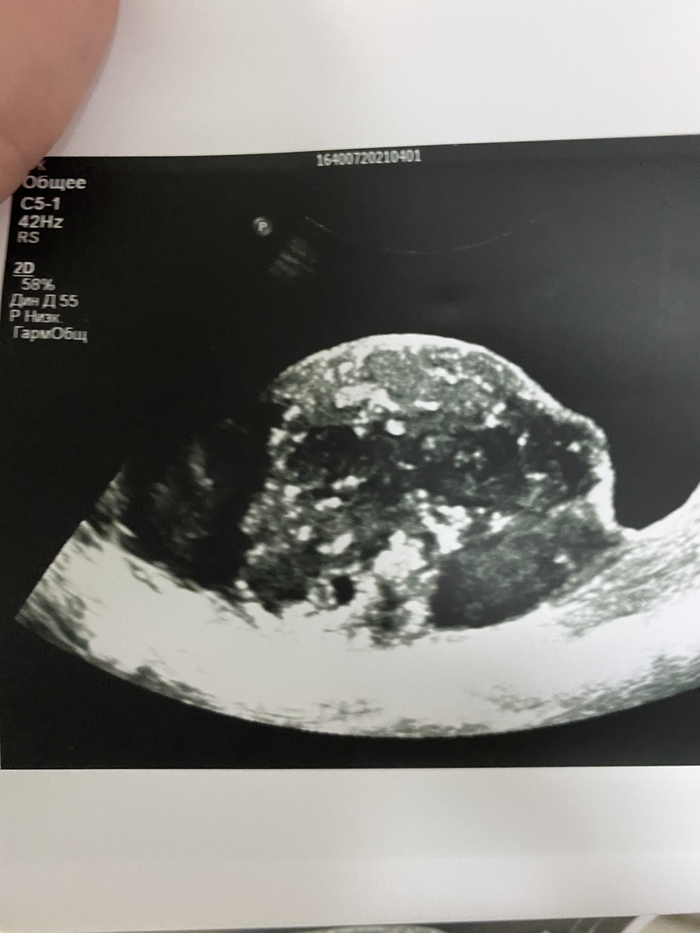

Было назначено УЗ-исследование вен нижних конечностей, которое исключило тромбоз, но при попытке вывести подвздошные сосуды, в полости малого таза оказалось случайной находкой объёмное образование, которое представляет из себя конгломерат из петель кишечника и предстательной железы.

Крайне сложно напугать врача, пусть и с не очень большим стажем в 10 лет. Но собственно, что ожидала, то и увидела. Увеличенная мошонка, несколько покрасневшая, но когда поставила датчик, то мне прям стало почти физически больно.

Не получается у меня прикрепить видео ультразвуковой картинки, как выглядят яички при раке.

Оставлю так и попробую вставить фото.

На фоне гидроцеле (скопления жидкости в мошонке) визуализируются идентичные друг другу изменённые яички и придатки, слабо дифференцируется ткань яичек, кровоток сохранен.